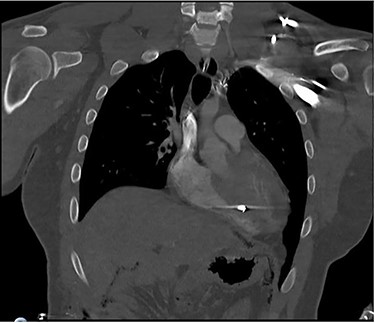

Coronal CT scan of the chest identifying bullet fragment in the interventricular septum.